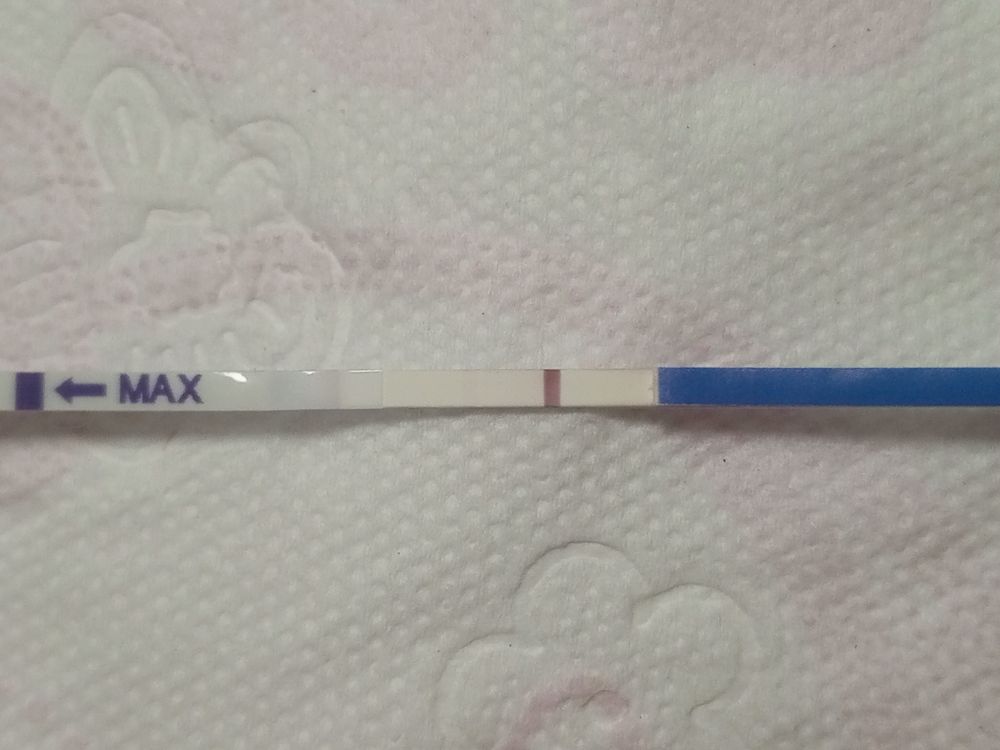

Тест после красных выделений

Девочки, ну помогите советом, я уже настроена на новый цикл, пришли месячные на 16 дпо сначала бледно розовые на следующий день были коричневые и вышел сгусток и кровить перестало только помазоло, а сегодня тест положительный, сегодня 5 дц, тошнит третий день если не поем, прям рвет 🤢, поясница болит, чувствую себя старухой... У меня было бхб с потверждеными тестами и хгч, но месячные приходили очень болезненно и шли долго а это почти три дня если считать то что мазоло и живот не болел от слово совсем

Ну тест вообще очень слабый. Скорее всего сорвалось.

Но вообще, лучше смотрите хгч в крови. Может быть это вообще было ИК

Вам на хгч кровь сдать нужно, на узи нет смысла ничего не увидят. А другой фирмы тест не хотите сделать?

Мама Лиля, на узи я не плодное яйцо искать хочу а узнать фазу цикла, то есть если это были месячные то и жт не будет и эндометрий тонкий, а хгч может быть и остаточный а его надо будет перепроверять

Маргарита , похоже сорвалось и пошли месячные, тесты потом отрицательные были но в этом цикле я забеременела, овуляция была в начале февраля, отслеживала